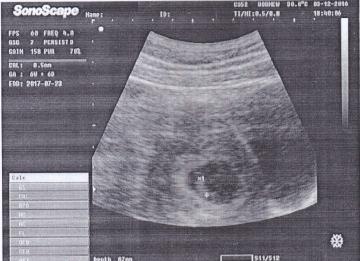

This is my first pregnancy and I am very much exited to know my baby's gender. This is my 7 week ultrasound abdominal scan report. I would be so grateful if you could see my scan report and tell if its boy or girl baby.

Attachment 33972

Pasteboard — Uploaded Image